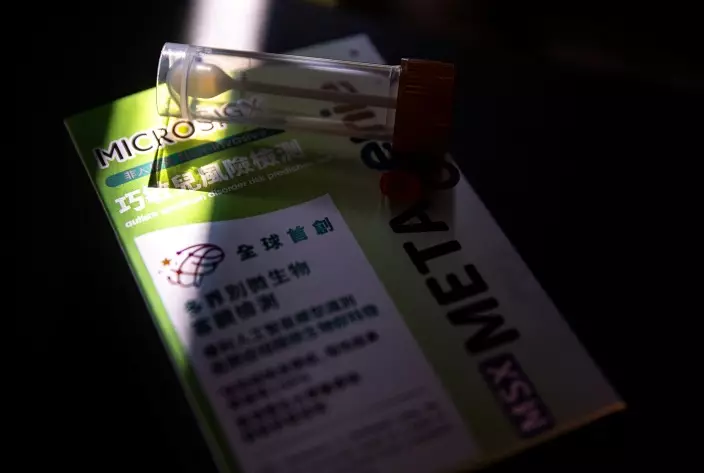

本港有逾2.2萬名兒童患閉症患者,近年更呈上升趨勢。中大醫學院聯同衍生公司「微識生物科技診斷有限公司」(MicroSigX)推出全球首創「多界別微生物技術」,透過檢測腸道微生物,檢測兒童患上自閉症的風險,有助及早介入及支援相關家庭。中大下月將與非牟利團體合作,為200名1歲半至4歲有疑似自閉症特徵的合資格兒童提供免費檢測。

中大醫學院開發全球首創的「多界別微生物技術」,揭示自閉症兒童的腸道微生物發展較同齡同性別兒童落後,相關研究成果2024年於國際期刊《自然—微生物學》發表。

中大醫學院副院長(研究)兼裘槎醫學科學教授黃秀娟表示,透過量度少量糞便樣的腸道微生物群特徵,包括細菌、古菌、真菌、病毒、微生物基因及代謝途徑等,再使用經驗證的人工智能模型,便可計算出自閉症風險評分 。有關專利技術已於2024年獲美國食品藥物管理局「突破性設備認證」,認可為全球創新且具潛力成為未來的自閉症輔助診斷工具。

MSX Metagenie®專利技術已於2024年7月獲美國食品及藥物管理局的「突破性 設備認證」,認可為早期識別兒童自閉症風險領域上達全球領先水平。中大提供

這項非入侵性診斷方案,已成功獲政府「產學研1+計劃」撥款支持,將科研成果轉化落地及進軍國際市場,計劃於內地及美國申請註冊,有望讓更多人受惠。

中大醫學院和MicroSigX將於明年1月與非牟利團體合作推出試點項目,為200名年介18個月至4歲、表現出疑似自閉症特徵但尚未確診的學前兒童,提供免費「多界別微生物技術」(MSX Metagenie®)檢測,家長可短訊9495 1894登記查詢。